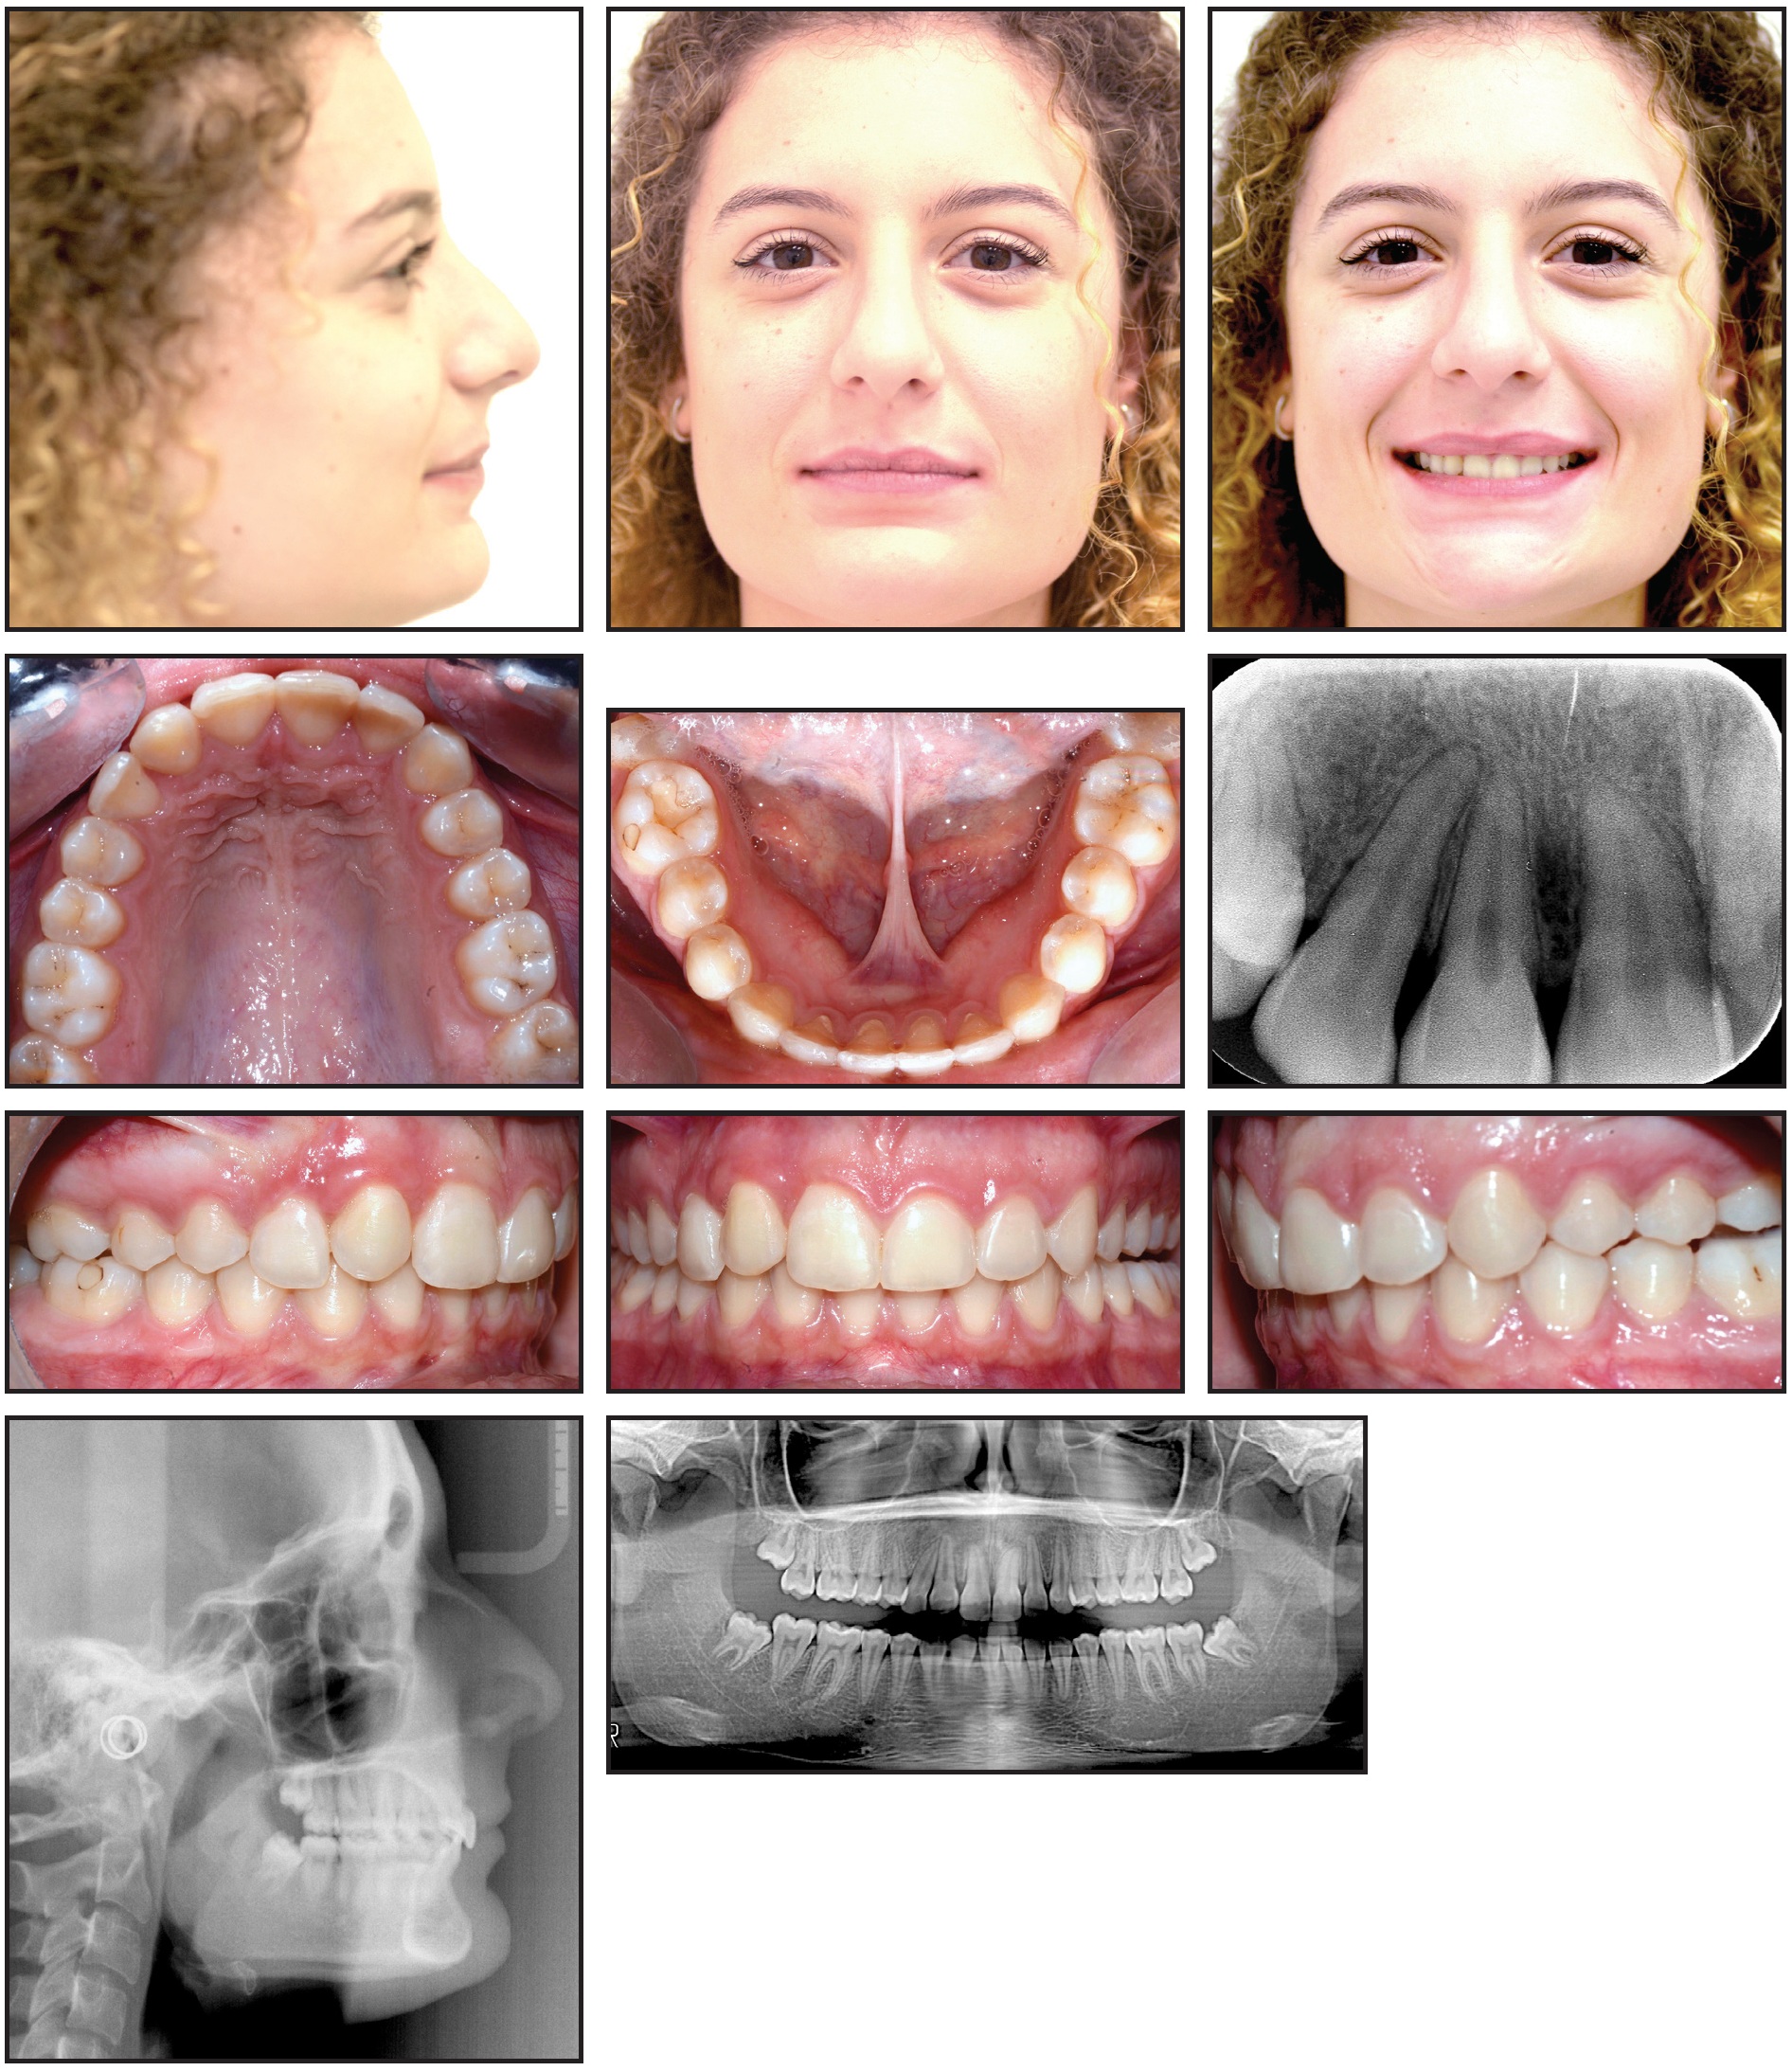

The total treatment time was 24 months, using 40 sets of aligners in the first phase and 27 in the second (Fig. 6).

Fig. 6 Patient after 24 months of treatment.

The patient complied with the treatment plan, and all objectives were achieved (Fig. 7).

Fig. 7 Final ClinCheck records.

The Class II malocclusion was corrected (Table 1), and the upper right canine was properly positioned in a functional relationship with the opposite arch.

Although the angulations of the maxillary canine roots were not ideal on the final panoramic x-ray, the results compared favorably with those of similar cases treated with fixed appliances alone. The upper lateral incisor roots maintained a “neutral” tip, as was seen before treatment. No root resorption was evident on the final panoramic or apical x-rays. The final canine torque seemed to be normal, despite the complexity of the movement performed by the clear aligners. The periodontal tissue was healthy overall, with appropriate alignment of the anterior gingival margins and a pleasant smile. Esthetic procedures to optimize detailing of the transposed teeth and smile display would be considered after skeletal maturation.

Clear Vivera* overlay retainers were delivered to be worn at night in both arches. The results remained stable one year after treatment (Fig. 8).